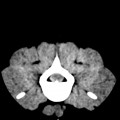

CT